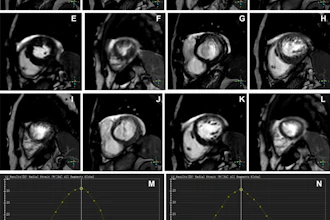

Cases of the Week

Check out our Cases of the Week!